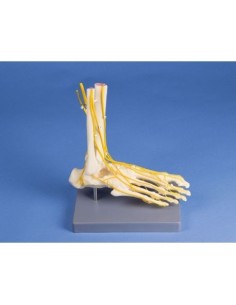

Esplora la nostra collezione dei migliori modelli anatomici degli arti superiori ed inferiori

La nostra esclusiva selezione di modelli anatomici delle estremità, meticolosamente prodotti dai leader del settore 3B Scientific ed Erler Zimmer, offre una rappresentazione fedele e dettagliata delle complesse strutture di mani e piedi. Questi modelli sono fondamentali per chiunque desideri esplorare l’anatomia delle estremità con una precisione senza pari, rendendoli strumenti didattici ideali per l’educazione e la pratica in ortopedia, fisioterapia e medicina dello sport.

Ortopedici, fisioterapisti, studenti di scienze della salute e istituti educativi si affidano ai nostri modelli per le loro esigenze educative e professionali, utilizzandoli per dimostrazioni pratiche e per migliorare la comprensione della meccanica e della funzione delle estremità umane.